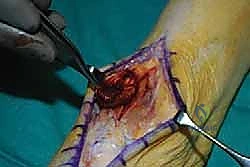

3. تقييم وتنظيف الوتر الممزق

يتم فتح الغمد الزليلي للوتر. في الحالات المزمنة، يجد الجراح أن طرفي الوتر قد تراجعا وتغطيا بنسيج ندبي متليف. يقوم الدكتور هطيف بتنظيف (Debridement) هذه الأنسجة الميتة حتى الوصول إلى نسيج وتري صحي وسليم، وتقييم حجم الفجوة.

4. حصاد وتر العضلة الباسطة لإبهام القدم (EHL Harvest)

يتم تحديد وتر EHL المجاور. يتم فصل الوتر من نقطة ارتباطه في إصبع القدم الكبير، مع الحرص على أخذ أطول مسافة ممكنة من الوتر لضمان وصوله المريح لنقطة التثبيت الجديدة.